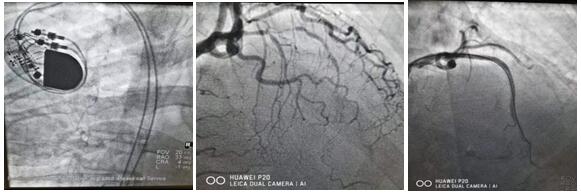

心腦血管疾病發(fā)病急,致死、致殘率高。春節(jié)期間僅心血管病院介入團(tuán)隊(duì)就完成了46例急診手術(shù),挽救了46個(gè)家庭的幸福。建議防疫期間有問(wèn)題及時(shí)咨詢就診,切不可因“疫”小病拖大病,增加家庭與社會(huì)負(fù)擔(dān)。

如有胸痛、胸悶、氣短(救護(hù)車24小時(shí)免費(fèi)接急診和住院患者)請(qǐng)撥打電話:胸痛中心:33788111 或 心臟綜合辦:33784588